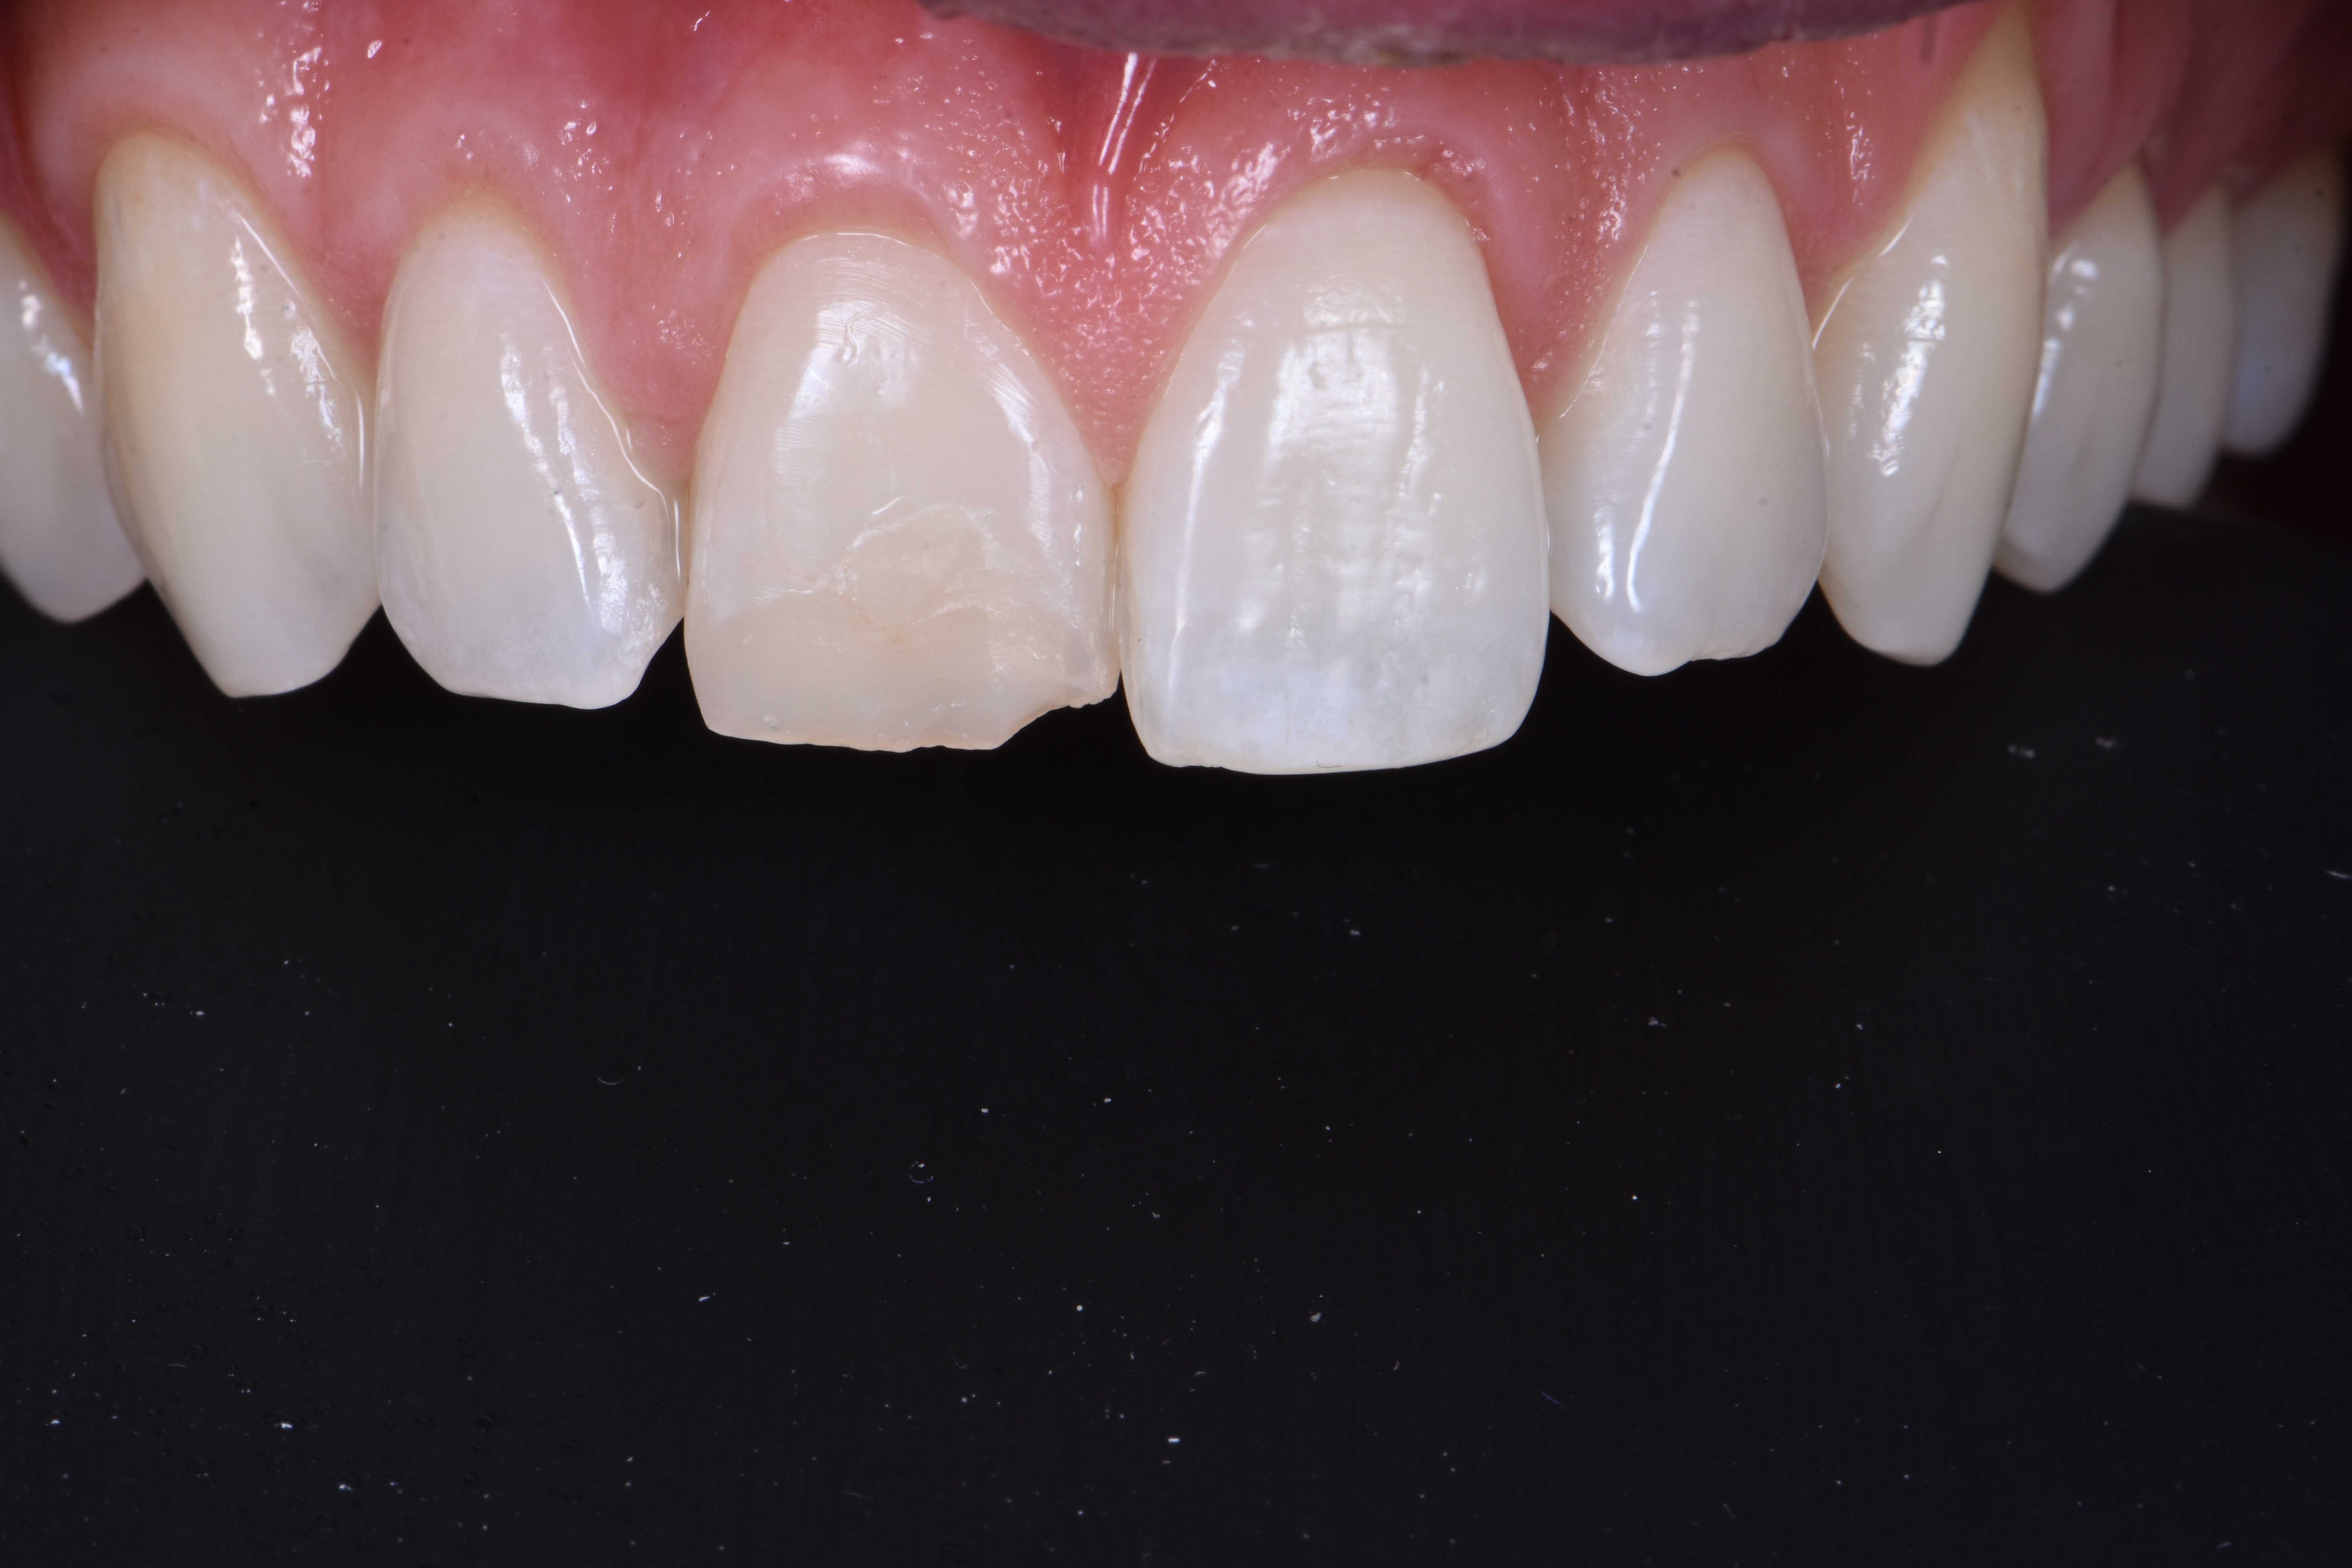

Korona zęba 11 była przebarwiona i ustawiona bardziej podniebiennie w porównaniu z koroną zęba sąsiedniego, tj. zęba 21 (ryc. 2).

Analiza estetyczna wykazała asymetrię położenia zenitów dziąsła między zębami 11 i 21. Po wykonaniu znieczulenia, z użyciem sondy periodontologicznej potwierdzono zaburzone bierne wyrzynanie typu 1A według klasyfikacji Cosleta i wsp. (1).